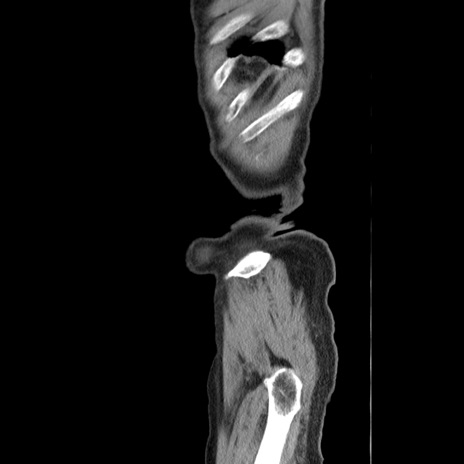

症例24(矢状断像)

【症例】80歳代男性

【主訴】左側腹部痛、嘔吐

【現病歴】本日早朝より左腹部に痛みあり。昼頃嘔吐認めたため、救急要請。

【既往歴】直腸癌(Mile手術)、胆摘

【身体所見】意識清明、BT 35.9℃、BP 221/93mmHg、SpO2 97%(RA) 、腹部:左ストーマ周囲に限局性の腹部膨隆あり。 膨隆部自発痛・圧痛あり・軟。

【データ】WBC 7700、CRP 0.09